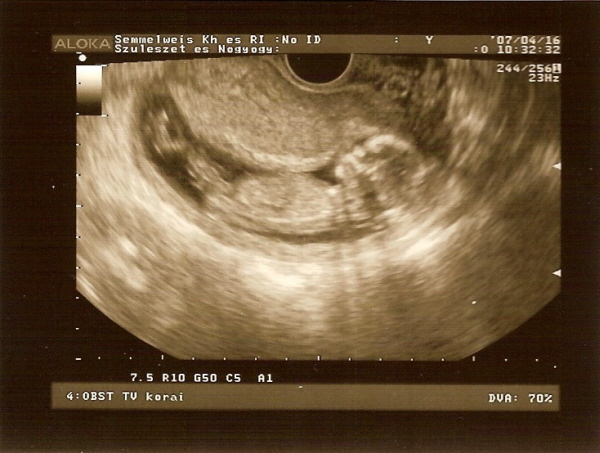

Csak a régieknek akik még emlékeznek rám, és kérték, hogy rakjak fel a babámról képet.És aki kérdezte, hogy milyen nemű lesz.Hát 99% hogy pici fiú.

Hát ő lenne az: